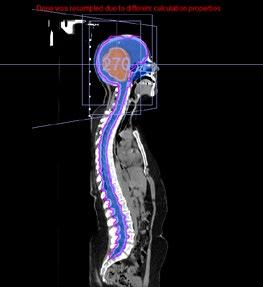

This issue includes six diverse, peerreviewed articles spanning rare case reports and forward-looking reviews. They include a rare presentation of immune checkpoint inhibitor-associated hydropneumothorax; a recurrent, aggressive, solitary plexiform neurofibroma with KRAS and AKT1 alterations; and a compelling case of unresectable giant pinealoblastoma responding favourably to induction chemotherapy followed by craniospinal radiotherapy. We also highlight a review of CAR-T cell-based immunotherapeutic strategies in hepatocellular carcinoma, a clinically significant case of aggressive angiomyxoma in term pregnancy, and a multi-omics exploration in non-small cell lung cancer aimed at advancing biomarker and pathway discovery.

133 Favourable Response of Unresectable Giant Pinealoblastoma After Induction Chemotherapy and Craniospinal Radiotherapy: A Case Report